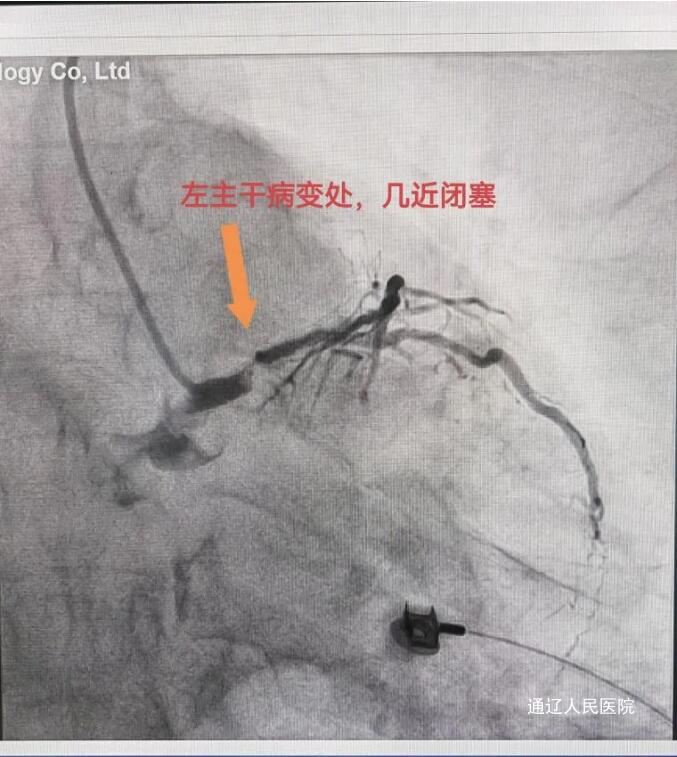

节假日期间,心内科的急诊手术并没有因节日来临而减少,大家依然忙碌着。近日,我院心内一科成功抢救一名65岁急性心梗患者,及时挽救了患者生命,有效提高了我院急性心梗患者的抢救成功率。患者阵发性胸痛持续10天,每次2-3分钟,未在意,6月9日突然加重,持续不缓解,急来我院就诊。行心电图检查提示广泛导联ST段下移,avR导联ST段抬高,接诊的心内一科李颖医生结合患者症状及心电图检查考虑左主干病变,病情危重,迅速启动导管室。紧急通知导管室医护人员做好术前准备工作;积极与患者家属沟通,详细解释病情的危险性及解决方案,征得患者及家属的同意后,迅速将患者送入导管室。患者冠脉造影如预测所示,左主干99%狭窄伴血栓形成,前降支、右冠均有程度不同的狭窄、重度钙化,回旋支从开口处即闭塞,为慢性闭塞。通常左主干+三支病变首选外科冠脉搭桥治疗,但本患者急性发病,持续胸痛,且左主干几近闭塞,死亡风险极高。对于这样的危急情况来说时间就是生命,尽早开通梗阻的血管,使心肌得到血液再灌注,是救治的关键。手术由吴哲主任医师和律桃园副主任医师进行,术前做好预案、充分准备,手术全程由导管室护士周文明、贾菲菲、陈瑜全力配合保驾护航,最终在大家的共同努力下,患者得到成功救治收入CCU进一步治疗。

冠状动脉左主干急性闭塞所致急性心肌梗死尤为凶险,大多迅速发展成心源性休克或死亡,有些患者发病不能及时到达医院,多表现为猝死,或者成功存活者随访的严重不良事件发生率仍较高。本例患者左主干99%狭窄,几近闭塞,命悬一线,在医护人员的共同努力下,通过介入治疗为患者争取到了一线生机。我院现已常规开展冠脉慢性闭塞病变、左主干病变、分叉病变、急诊介入等高难度心血管介入手术。今后,通辽市人民医院将持续依托强大的技术实力和专家团队优势,为患者带去更便捷、优质的医疗服务,为患者生命保驾护航。